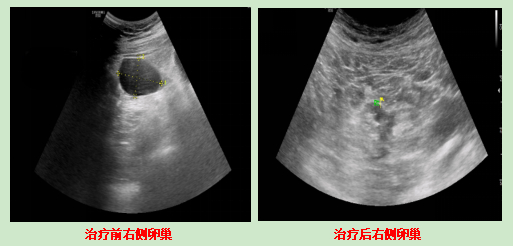

·卵巢B超:双侧都有囊肿,左侧7个多公分,右侧5个多公分。

·左侧卵巢那个7cm的囊肿,缩小到5cm左右。

·左侧卵巢囊肿只剩1公分多,右侧完全消失;